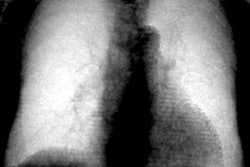

Throughout this year's COVID-19 pandemic, chest CT has proven to be a valuable tool for diagnosing the illness in particular clinical situations -- such as when reverse transcription polymerase chain reaction (RT-PCR) testing isn't readily available or results are delayed.

But the modality has also shown value in assessing the severity of the disease and evaluating ongoing conditions that can plague recovered patients, especially when combined with artificial intelligence (AI), according to several presentations in a scientific session on chest imaging delivered on Sunday at the RSNA 2020 meeting.

In the third Sunday afternoon lecture, a team led by Dr. Eduardo Jose Mortani Barbosa of the University of Pennsylvania in Philadelphia noted that COVID-19 patients may develop airspace disease, in which alveolar air is replaced by fluid, pus, or blood and the condition continues beyond four to six weeks after treatment.

Chest x-ray is the go-to for evaluating this condition, but it tends to have limited sensitivity. While chest CT is more accurate, it's not used routinely to assess airspace disease.

Barbosa and colleagues developed a way to quantify the percentage of lung volume involved in airspace disease on chest x-rays using a convolutional neural network (CNN) algorithm based on 1,000 chest CT scans of COVID-19 patients. The researchers used a test set of 86 patients with positive RT-PCR results who had chest CT and chest x-ray less than 48 hours apart.

The algorithm projected the CT exams' 3D lung and airspace disease segmentation on reconstructed x-rays using quantitative maps of lung tissue thickness and manifestations of airspace disease.

The group found that the CNN-reconstructed x-rays quantified airspace disease at least as well as the human CT exam readers: CT had a rate of 24.3%, while the CNN's digitally reconstructed x-rays had a rate of 24.4%.

"This approach may increase efficiency and consistency in chest x-ray interpretation of COVID-19 patients, especially when applied to longitudinal chest x-ray data to inform management," Barbosa concluded.